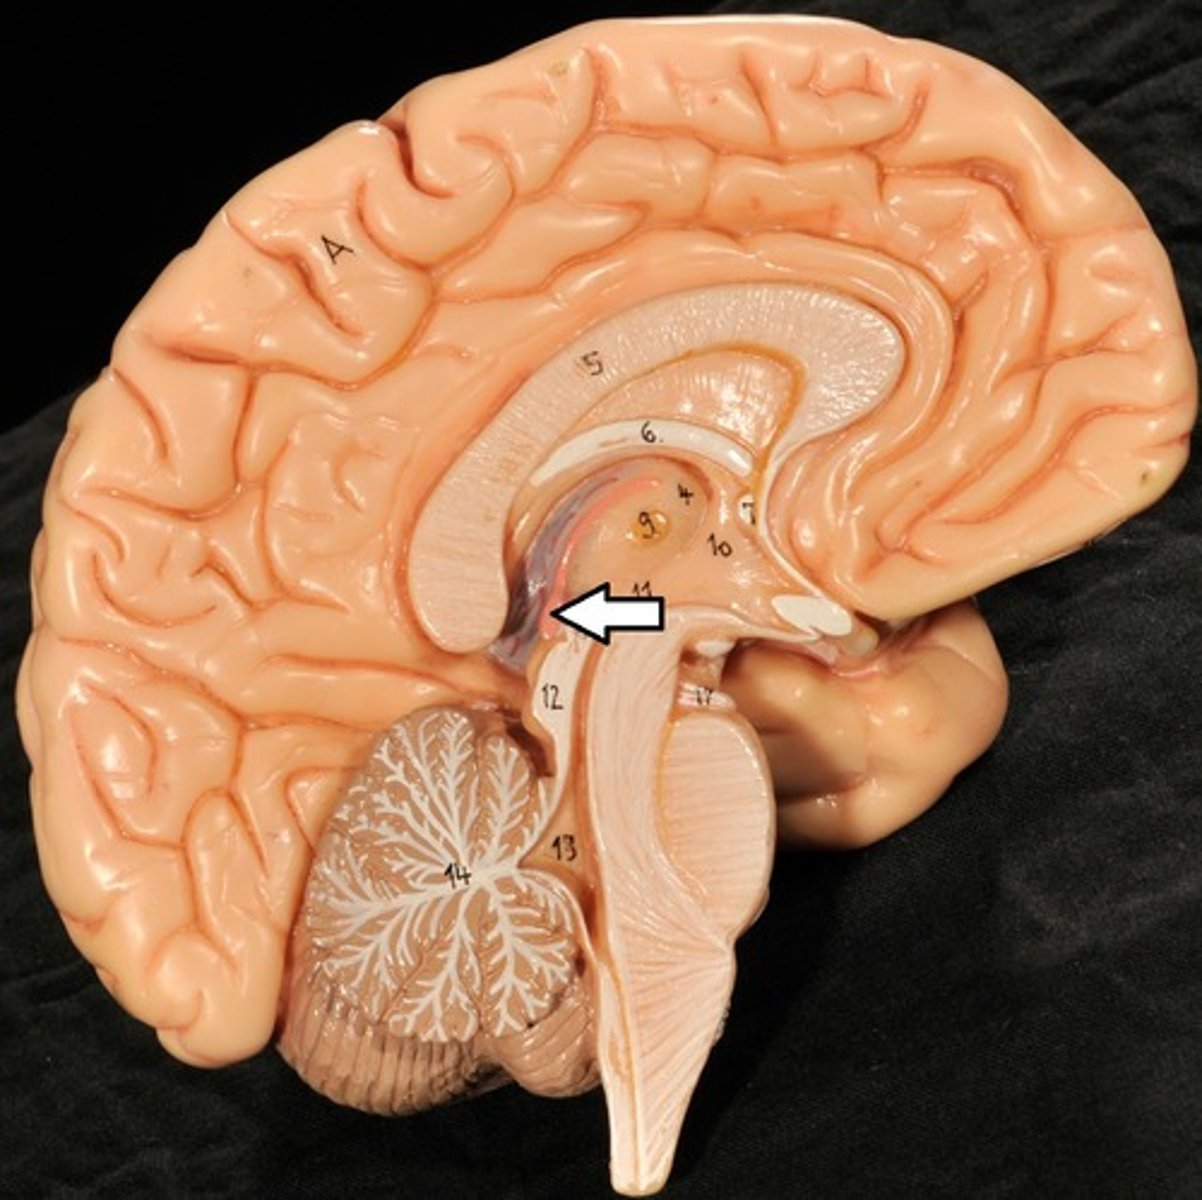

Ventricles

1) Right & left lateral ventricles:

-Anterior, Posterior & inferior horns

2) 3rd Ventricle, Cerebral aqueduct, 4th ventricles

4) Apertures (Narrow openings) into subarachnoid space of spinal cord

Anterior Horns

Posterior Horns

Inferior Horns

3rd Ventricle

4th Ventricle